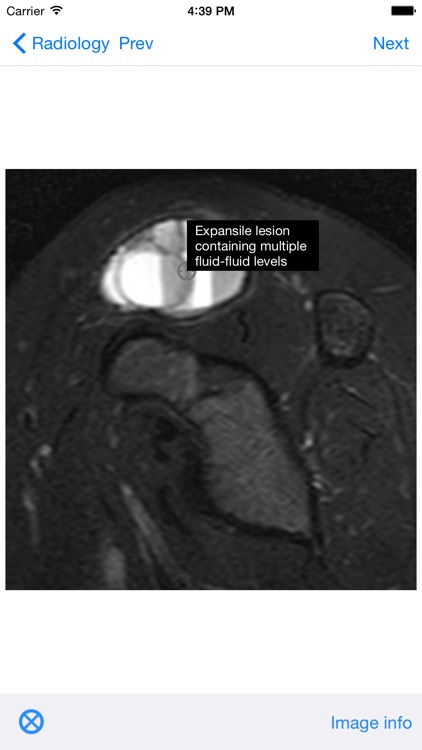

BoSTT brings the user a real experience of frequent and rare, typical and more unusual cases of bone and soft tissue tumours. Each case has a clinical history, high resolution radiology and pathology images, diagnosis, treatment and learning points.